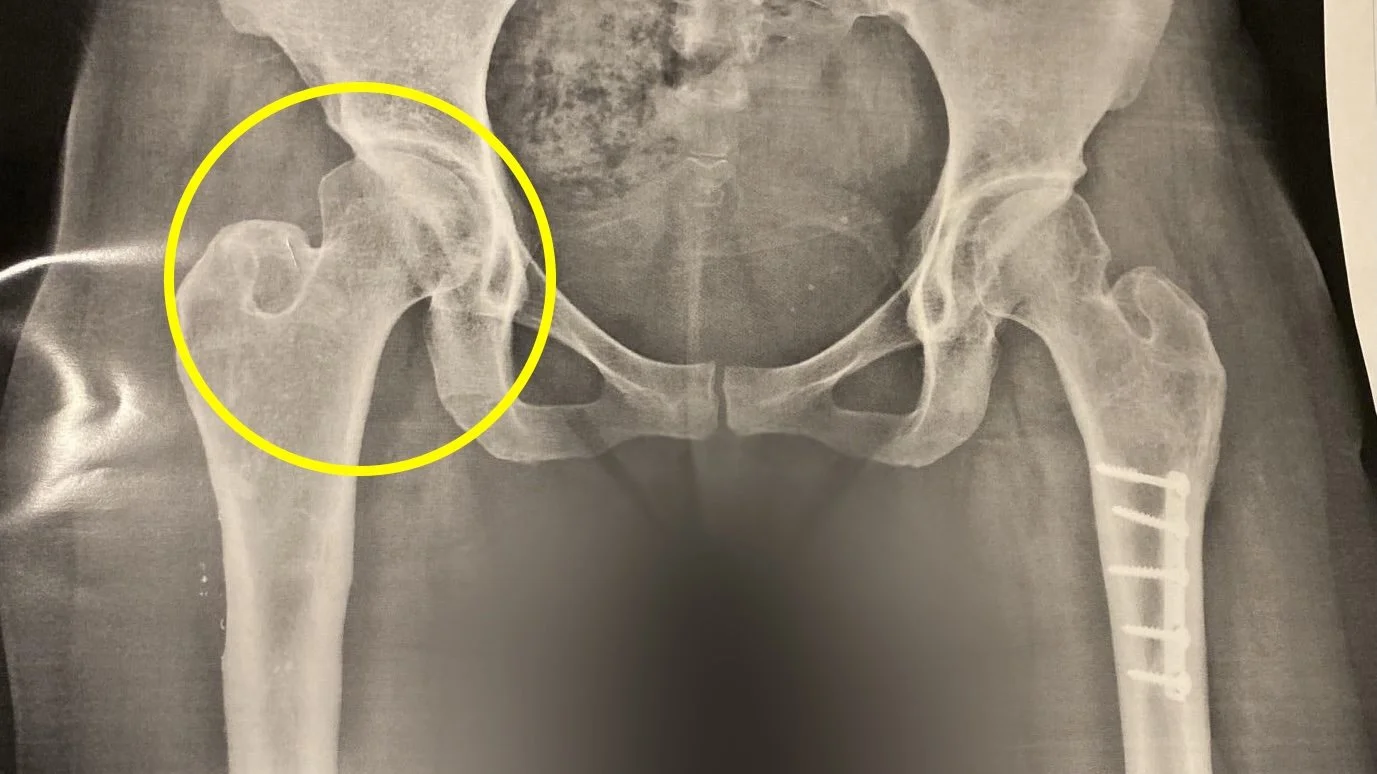

Tathiana was born with hip dysplasia and was undiagnosed until later childhood. She had two extensive surgeries when she was young, which involved long hospital stays far from home, leg traction, and full-body casts. She carried plates and screws in her legs for decades (in the picture, you can still see the hardware in her left leg), as well as a slight leg-length difference. After our daughter was born, she had another surgery to remove the hardware in her right leg to help with the inflammation and pain that resulted from her pregnancies.